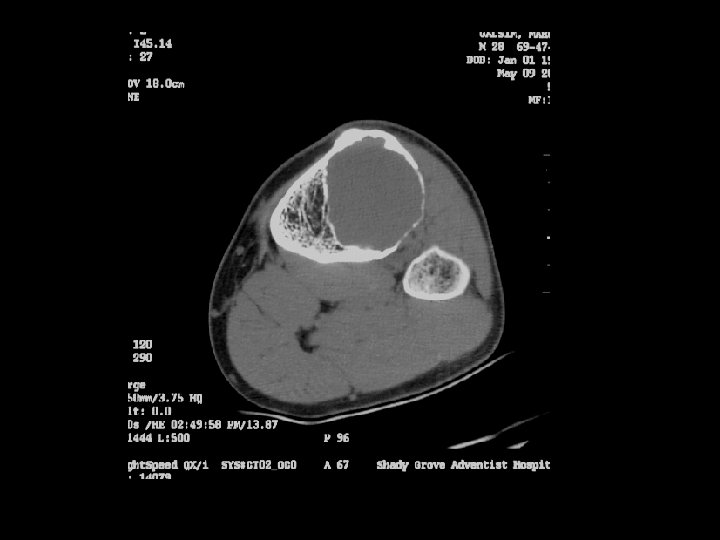

Cross-sectional imaging Pictures are pretty, but diagnosis • established at histology MRI best for most tumors • optimal results at sites with experience – Role of CT limited • may assist in assessing tumor matrix – useful in directing biopsy –

A 14 year old boy presents with pain and a mass above the knee. Take a look at the AP and lateral radiographs first.

Example 4*, 35 y/o F, GCT